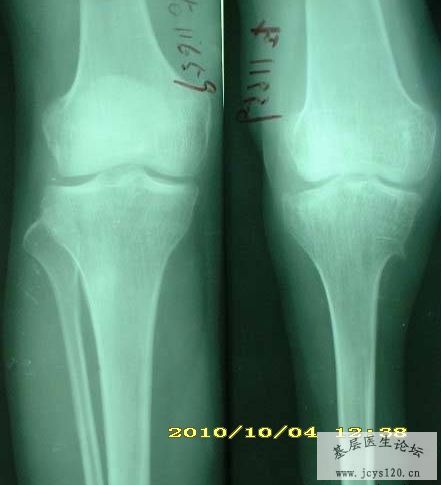

同行帮给看一下这个造影,需要怎么治疗比较理想